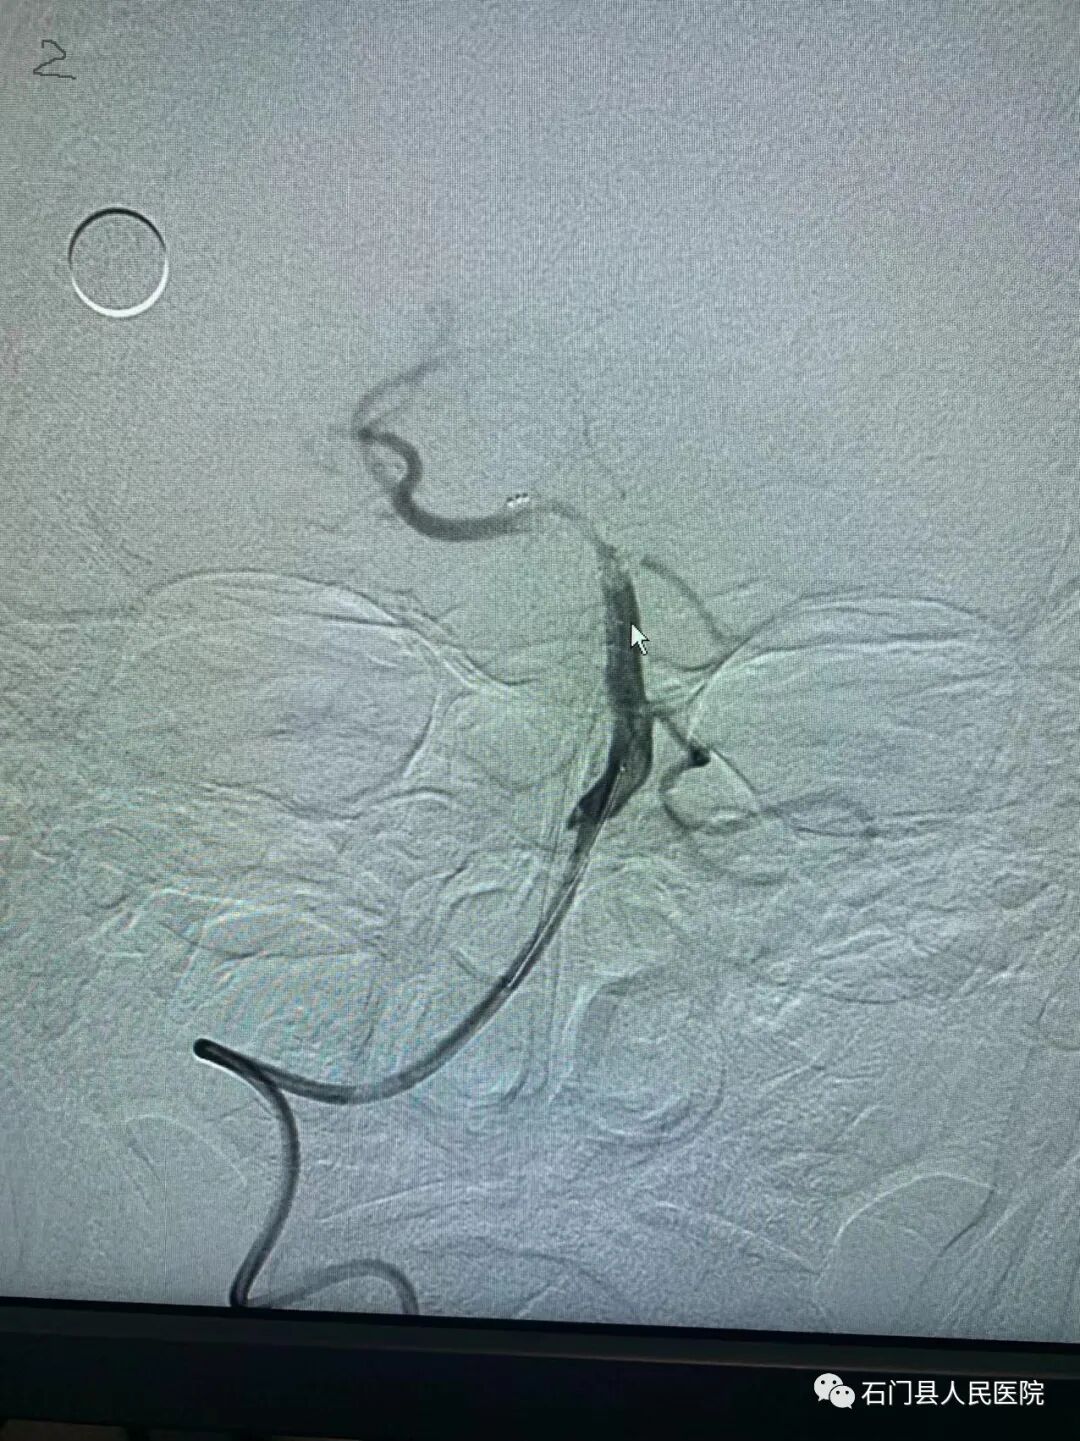

经股动脉全脑血管造影术、颅内动脉瘤栓塞术、颈动脉取栓术及支架植入术。